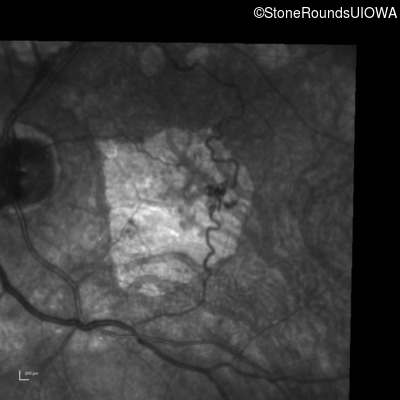

Fluorescein Angiography - Right - 20/100 -1

Exemplar

Fluorescein Angiography - Left - 20/40 -1